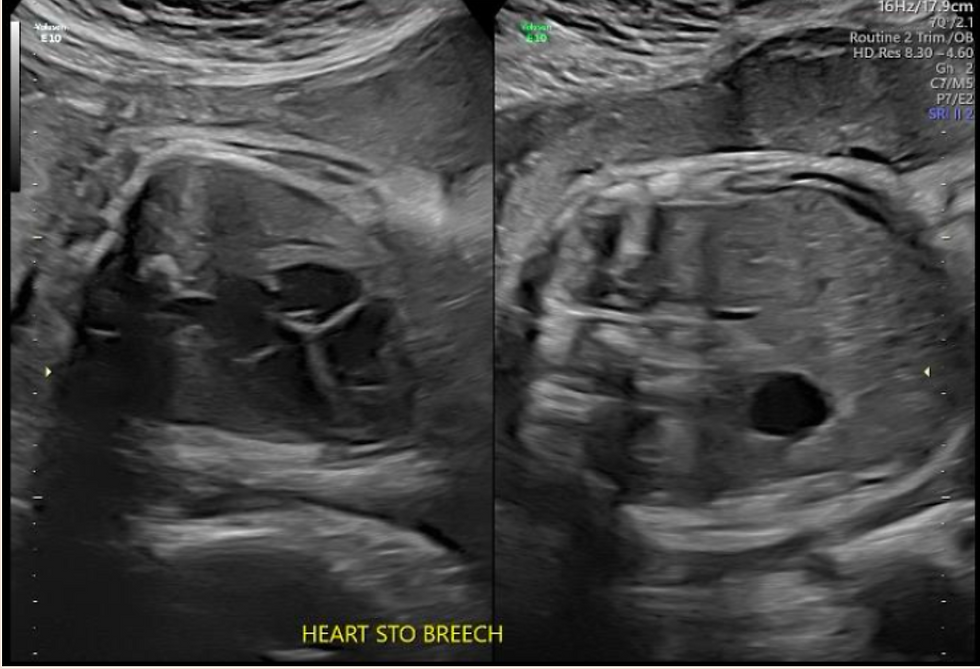

As Anna has Type 4 OI, she had in-utero findings that were monitored by the Maternal Fetal Medicine team. She had demineralization of bones, healing fractures in the femur, bowing of the femurs (but not humeri), and was measuring small for gestational age. It is important to note that she measured small because her long bones are bowed, underestimating their true length, and both her parents are under 5 feet, meaning her interval growth was appropriate but low against the population average.

At each serial ultrasound appointment, the sonographer evaluated existing fractures during and looked for new breaks, particularly in the long bones. It is, therefore, so important to really zoom up the images so that the area of focus takes up 80-90% of the screen, as this can be extremely subtle. The sonographer would also monitor ribs to make sure they were structurally sound and growing properly, as pulmonary hypoplasia is a serious complication.

Sonographic Findings Frank Breach

From a delivery perspective, it is important to note that breech lie is significantly higher among OI fetuses, which may impact delivery. Interestingly, multiple studies are showing that there is no significant difference between cesarean versus vaginal delivery in terms of non-lethal fetal fractures at the time of delivery. In other words, cesarean section does not significantly reduce the risk of a fracture at birth (Bellus et al, 2016; Cubert et al, 2001). My friend opted for a c-section for a couple of reasons. The first is that, if all risks were equal between vaginal and c-section delivery, she felt that with a c-section, the OB/GYN [jO1] would have at least some control over external factors. The second reason is that the baby was presenting Frank Breach, and therefore, a c-section was recommended regardless of the underlying diagnosis.